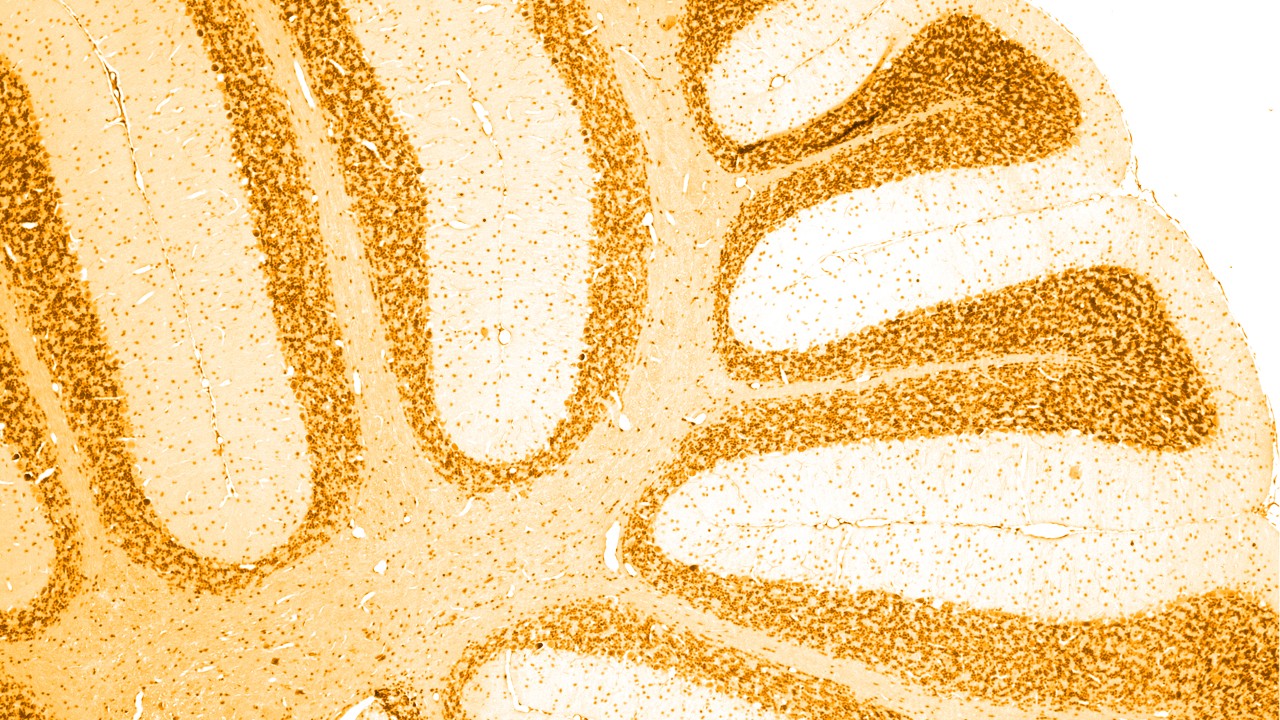

痴呆有很多种诱因,其中最常见的是阿尔茨海默病,和大脑中异常“淀粉样蛋白斑”及“神经纤维缠结”累积相关。其他一些特定的痴呆疾病也有大脑中异常“神经纤维缠结”累积;作为一类疾病,被称为“Tau蛋白病”。